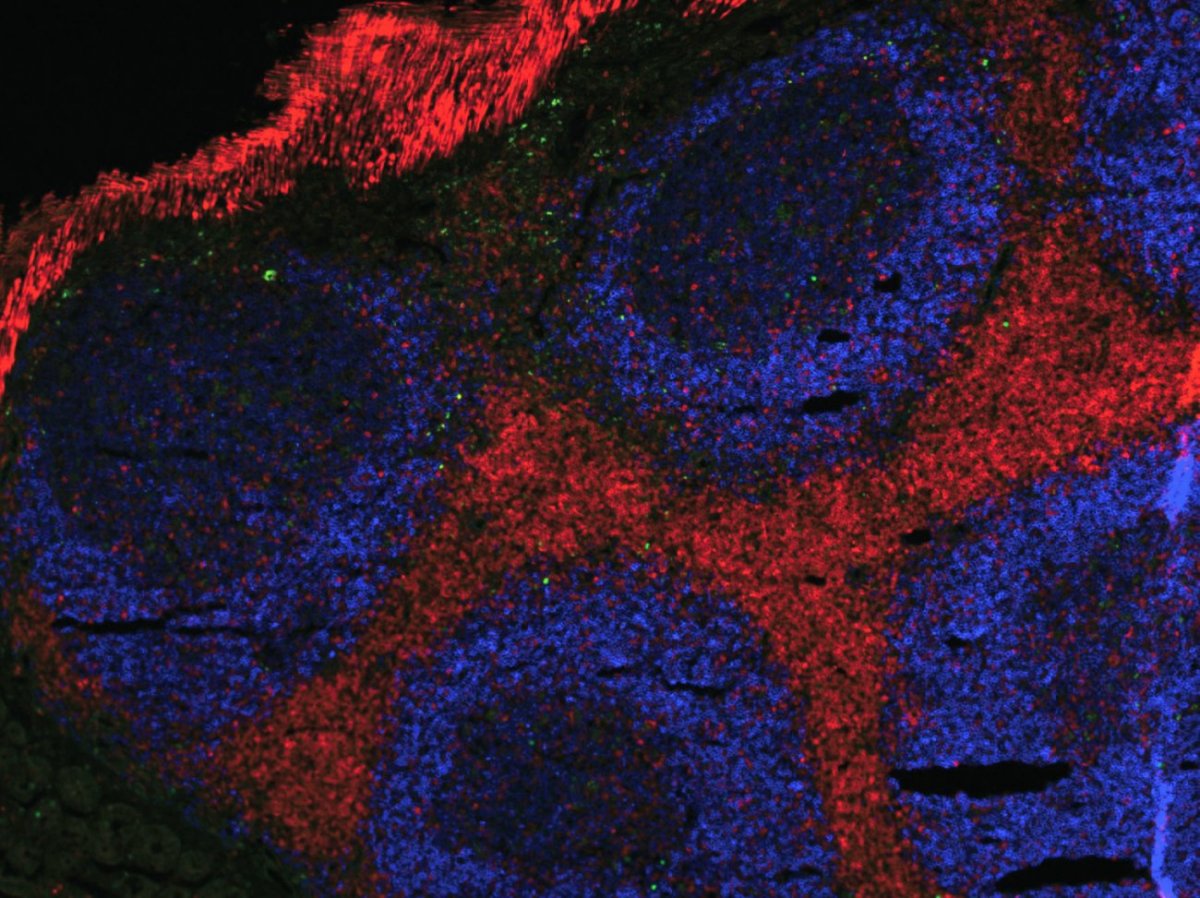

Notre système immunitaire n’est pas statique : il évolue tout au long de la vie, façonné par des facteurs comme l’âge, le sexe ou l’histoire vaccinale. Grâce à des technologies de pointe comme le single-cell sequencing, ces variations peuvent être analysées, révélant les mécanismes du déclin immunitaire lié à l’âge.

Le séquençage de cellule unique (single-cell sequencing) est une technologie de pointe analysant l’ARN cellule par cellule, révélant leur diversité et leur fonctionnement individuel. Grâce à des systèmes microfluidiques, elle identifie des sous-populations cellulaires – comme des cellules tumorales résistantes aux traitements – ou des sous-populations rares apparaissant avec l’âge indétectables par les méthodes classiques. En oncologie, elle permet de distinguer les cellules saines des cellules malignes et d’affiner les cibles thérapeutiques. Cette approche révolutionne les diagnostics, les traitements personnalisés et la compréhension des maladies.

En exposant in vitro les cellules sanguines de 380 individus de la cohorte “Milieu Intérieur” à des pathogènes comme le SARS-CoV-2 ou le virus de la grippe, il a été démontré que les personnes âgées présentent une réponse immunitaire affaiblie, notamment en raison d’une production réduite d’interféron alpha, une protéine cruciale pour bloquer la réplication virale. « Parallèlement, l’analyse de l’ensemble des gènes montre que les lymphocytes T CD4 sont le type cellulaire le plus impacté par l’âge », complète le chercheur.

Leurs travaux confirment également que les femmes bénéficient d’une réponse immunitaire plus robuste que les hommes, un paradoxe connu sous le nom de mortality-morbidity paradox : bien qu’elles vivent en moyenne plus longtemps, elles sont aussi plus sujettes aux maladies auto-immunes. « Chez les femmes, les cellules immunitaires innées, comme les cellules myéloïdes, réagissent plus vigoureusement aux virus, avec une expression accrue de gènes proinflammatoires», précise le chercheur. Cette supériorité s’explique en partie par leurs deux chromosomes X : certains gènes échappent à l’inactivation du second chromosome X, leur offrant un avantage immunologique.

À l’inverse, les hommes âgés de plus de 60 ans perdent souvent leur chromosome Y (jusqu’à 50 % dans certains cas), un phénomène que l’équipe a associé pour la première fois à une réponse immunitaire affaiblie. « Cette perte pourrait expliquer pourquoi les hommes sont plus vulnérables aux infections sévères en vieillissant », souligne Marwan Sharawy. Ces découvertes ouvrent des perspectives prometteuses pour préserver une immunité robuste malgré l’âge. « Si nous parvenons à comprendre pourquoi certaines personnes âgées conservent un système immunitaire performant, nous pourrons peut-être reproduire ces conditions chez d’autres », espère Marwan Sharawy. Ses résultats pourraient inspirer de nouvelles approches thérapeutiques, comme la stimulation ciblée de l’interféron alpha. « L’objectif n’est pas seulement de vivre plus longtemps, mais de vieillir en meilleure santé », résume-t-il.